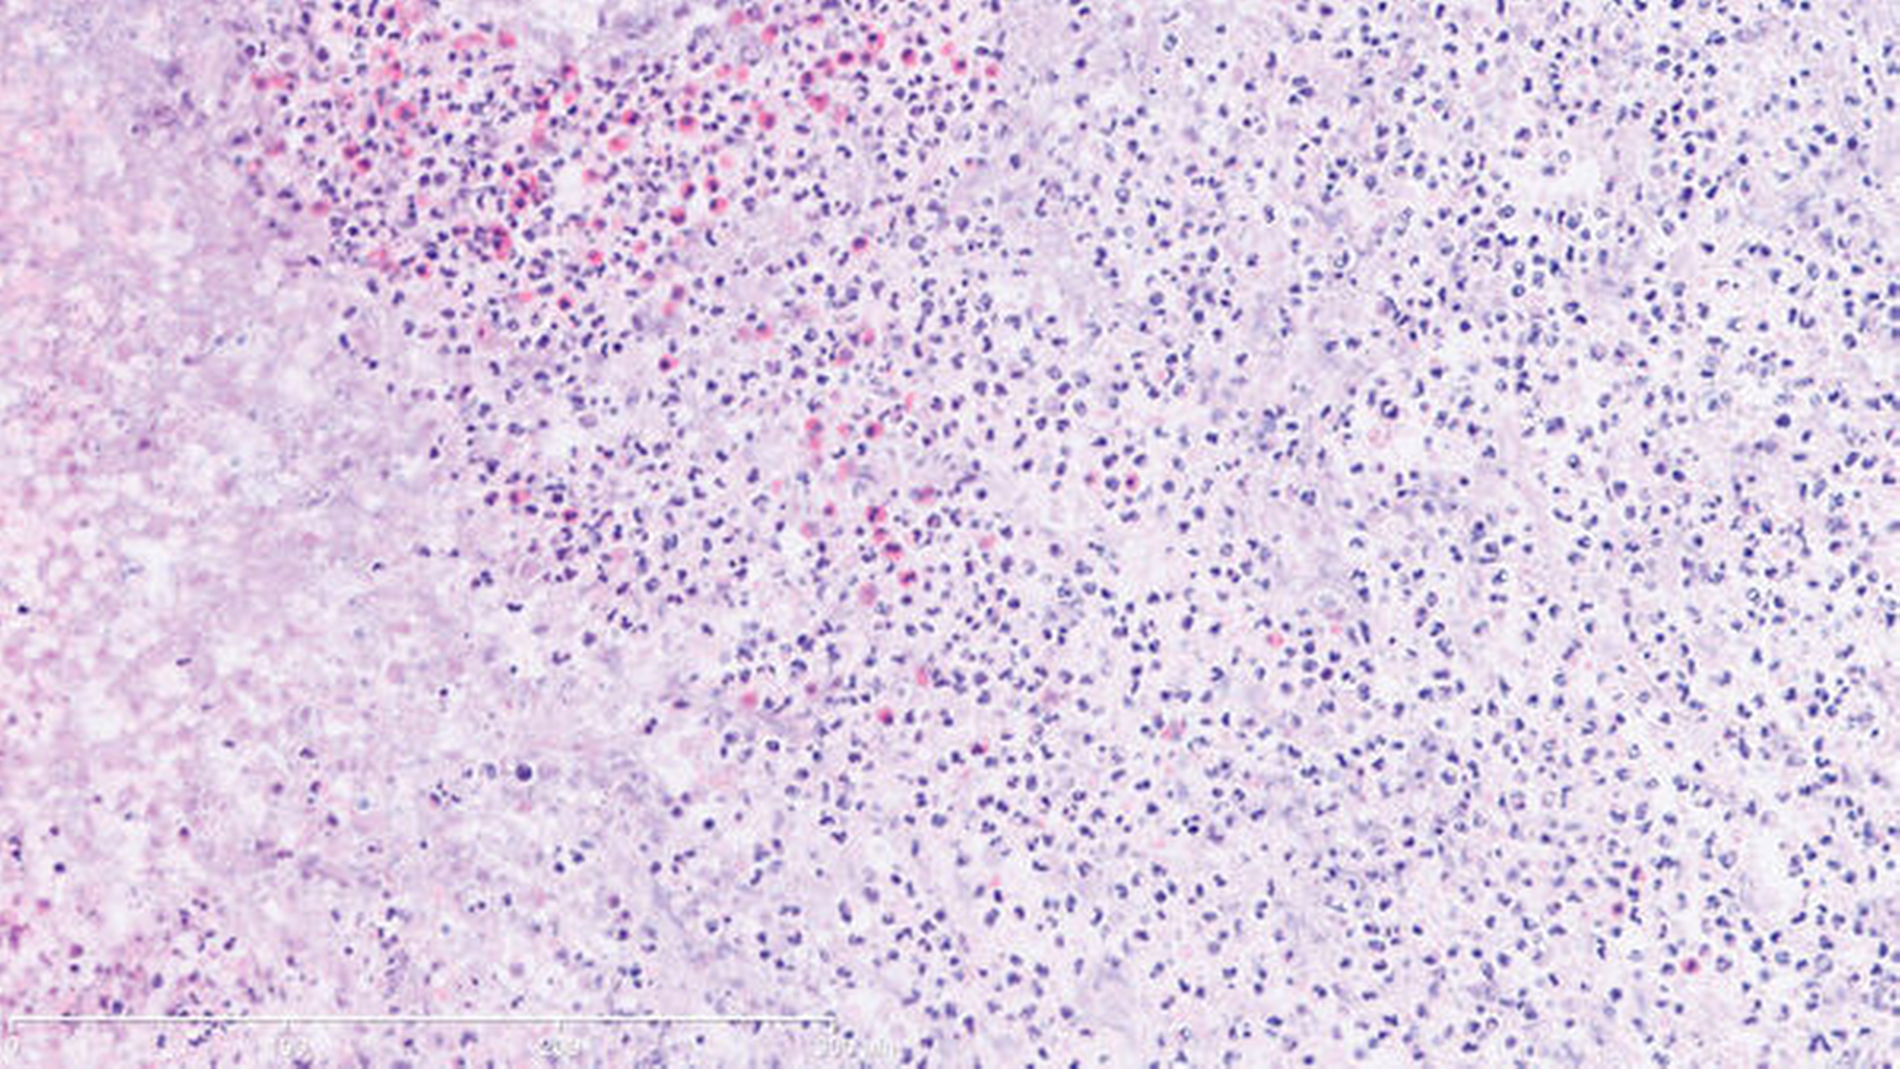

Bei der Besprechung am zehnten postoperativen Tag war der Patient beschwerdefrei. Eine orale Ernährung war mit der Tiefziehschiene suffizient möglich. Die histologische Untersuchung von mehreren intranasalen Proben ergab keinen Anhalt für eine solide Neoplasie oder für ein Lymphom. Es zeigte sich eine teils chronische, teils fokal floride Entzündung mit Ulzeration und Nekrosen, außerdem eine deutliche Eosinophile. Granulome oder eine eindeutige Vaskulitis lagen nicht vor (Abbildung 4). Bei negativer Infektionsserologie, unauffälligen Routinelaborwerten (nur leichter CRP-Anstieg 32,5 mg/l – Norm < 5 mg/l) und einem hochgradigen klinischen und histologischen Verdacht auf M. Wegener wurde der Patient zunächst in die heimatnahe Klinik für internistische Rheumatologie zur weiteren Abklärung und systemischen Therapie überwiesen. Der chirurgische Defektverschluss mittels Palatoplastik wurde in Rücksprache mit den internistischen Kollegen nach Einleitung der Remissionsinduktion und Ausschleichen der entsprechenden Medikamente in circa sechs Monaten geplant.

Laborchemische Untersuchungen zeigen außer der stark beschleunigten Blutsenkungsgeschwindigkeit keine eindeutigen Befunde. Lediglich die Erhöhung von c-ANCA mit Anti-Proteinase-3-Zielantigen in Zusammenschau mit den klinischen, radiologischen (CT-Thorax) und histologischen (Biopsie von NNH, Lunge, Niere) Befunden erlauben die sichere Diagnosestellung. Eine c-ANCA-Erhöhung findet man letztendlich nur in bis zu 50 Prozent der Fälle im Initialstadium und erst im fortgeschrittenen Stadium in 95 Prozent der Fälle. Darüber hinaus findet man falsch positive c-ANCA-Werte durchaus bei bestimmten Infektionen (zum Beispiel Hepatitis C) und neoplastischen Prozessen. Während die Lungen- und Nierenbiopsien im generalisierten Stadium meist ganz typische histologische Befunde mit Granulombildung und Vaskulitis liefern, sind die Proben aus den Nasenhaupt- und Nebenhöhlen im lokal begrenzten Initialstadium häufig nicht repräsentativ und durch eine floride, einschmelzende Entzündung mit Nekrosen gekennzeichnet. Differenzialdiagnostisch sollte M. Wegener von einer anderen, jedoch mit 1:1.000.000 deutlich selteneren Vaskulitis (Goodpasture-Syndrom) abgegrenzt werden. Dabei kommt es vordergründig zum direkten Nieren- und Lungenbefall [Suttorp et al., 2016].